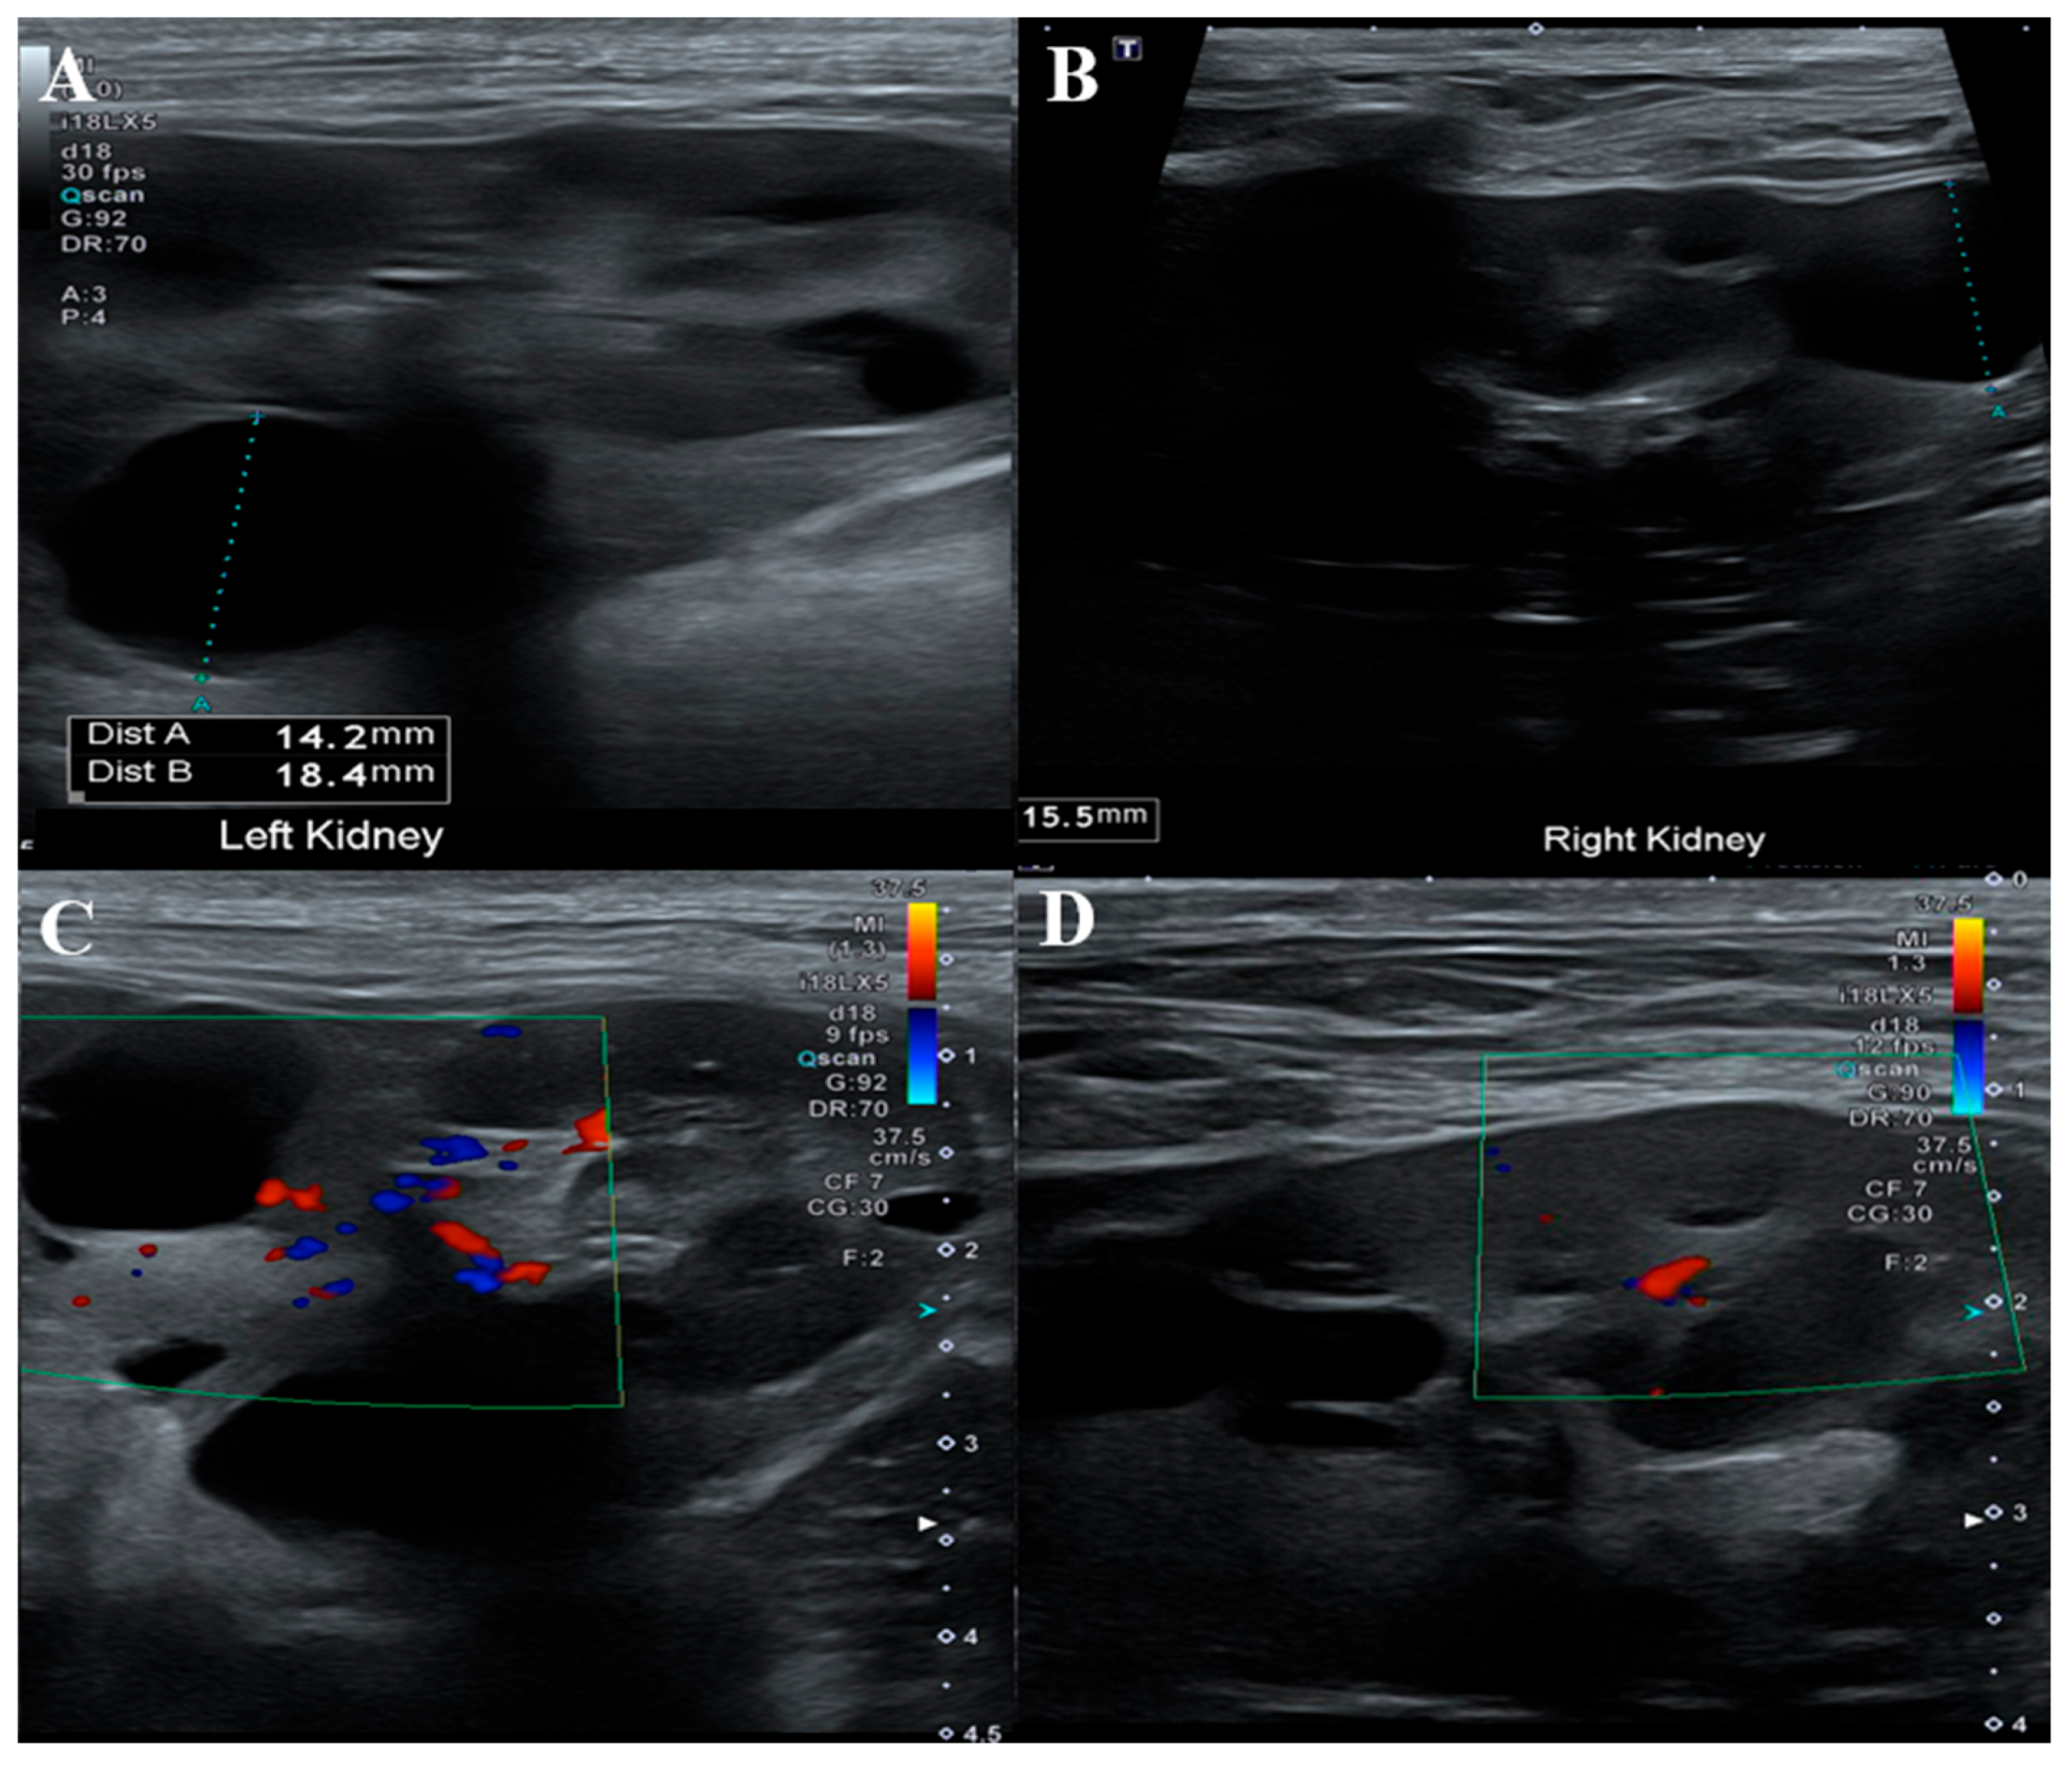

| Case at present | Bichon Frise | Renal cysts suspected; no biopsy performed | Negative | No FLCN mutation; variants found in BRCA2 genes |